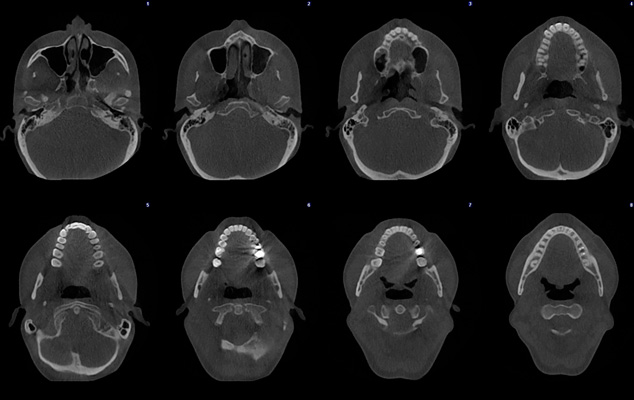

Immagini a ultra basso dosaggio - Cranio completo

Planmeca ProMax 3D Mid - FOV Ø 200 x 170 mm. - Dimensioni voxel 300 µm / 600 µm - Dosaggio effettivo del paziente 14,7 µSv